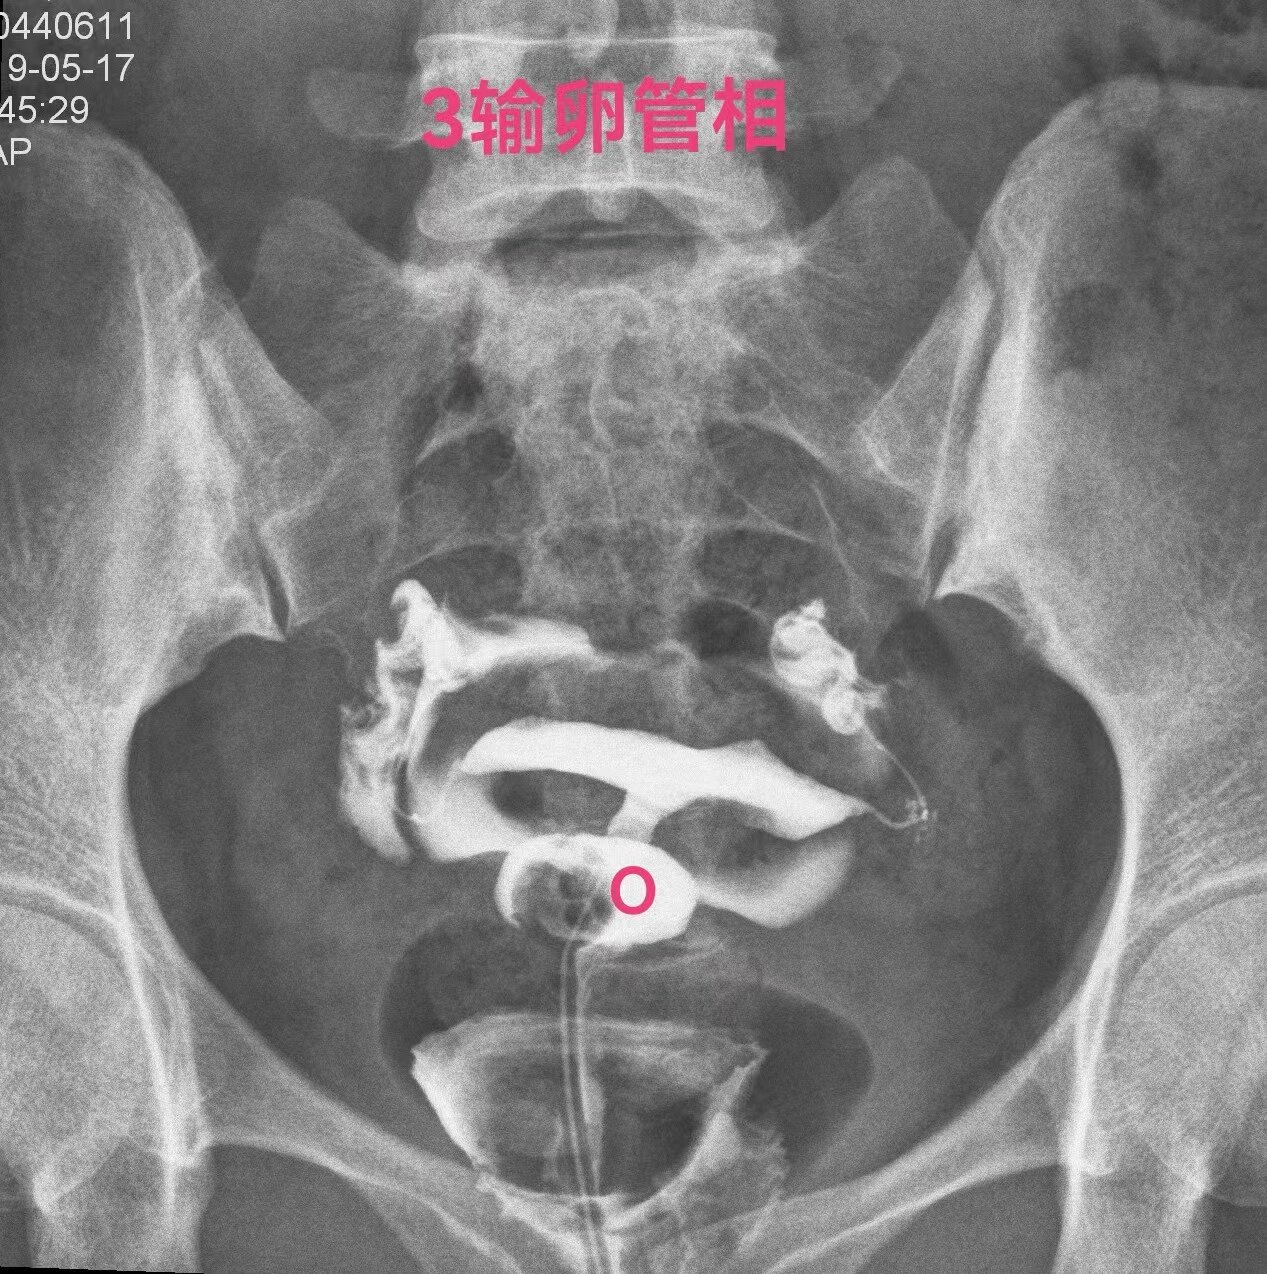

下面一例造影图就可以看直观看懂憩室导致经血流出不畅

弥散相子宫腔内造影剂完全流出来了,憩室内还有较多造影剂充满憩室腔。月经血流出相仿。